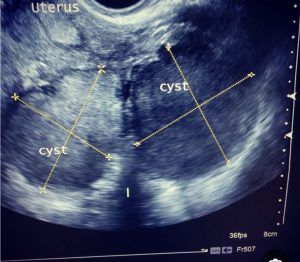

الحمل خارج الرحم (Ectopic Pregnancy) هو انغراس البويضة المخصبة خارج التجويف الطبيعي للرحم، وغالبًا داخل قناة فالوب، وقد يحدث في حالات أقل داخل المبيض أو عنق الرحم أو تجويف البطن. تكمن خطورة هذه الحالة في أن تلك المواضع لا تمتلك القدرة التشريحية أو الدموية اللازمة لاستيعاب نمو الحمل، ما يؤدي مع استمرار الانغراس إلى تمزق الأنسجة وحدوث نزيف داخلي حاد قد يهدد حياة المرأة خلال وقت قصير.

يعتمد تشخيص الحمل خارج الرحم على الجمع بين تحليل هرمون الحمل في الدم (β-hCG) والمتابعة بالموجات فوق الصوتية لتحديد موقع الحمل. وعند تأكيد التشخيص، يُتخذ القرار العلاجي سريعًا بناءً على حالة المريضة ومرحلة الحمل.